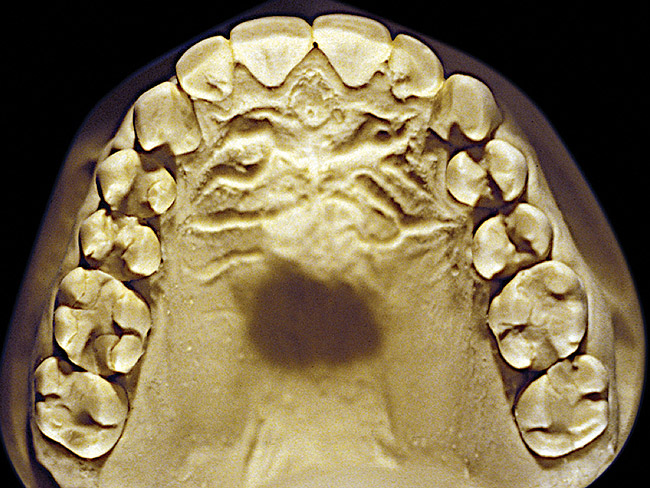

Figure 4  Advanced NCLTS from bruxism, maxillary arch.

The patient shown in Figure 3 and Figure 4 exhibited severe NCLTS from bruxism. Examination of the casts indicated that the NCLTS was progressively greater toward the anterior teeth. Cupping and cratering was not present because there was no secondary cause. Figure 5 and Figure 6 detail another bruxism patient, but to a lesser degree and one with cupping/cratering caused by toothpaste. The cups or craters were not caused from bruxism because the teeth could not touch the bottom of the invaginations. In both featured patients, upon hand-articulating the casts, the NCLTS facets matched up and the diagnosis of bruxism was confirmed.